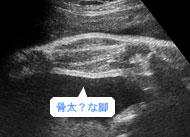

将来はアスリートかな?ふくらはぎの2本の骨もずいぶん太くなりました。(妊娠36週)

将来はアスリートかな?ふくらはぎの2本の骨もずいぶん太くなりました。(妊娠36週)